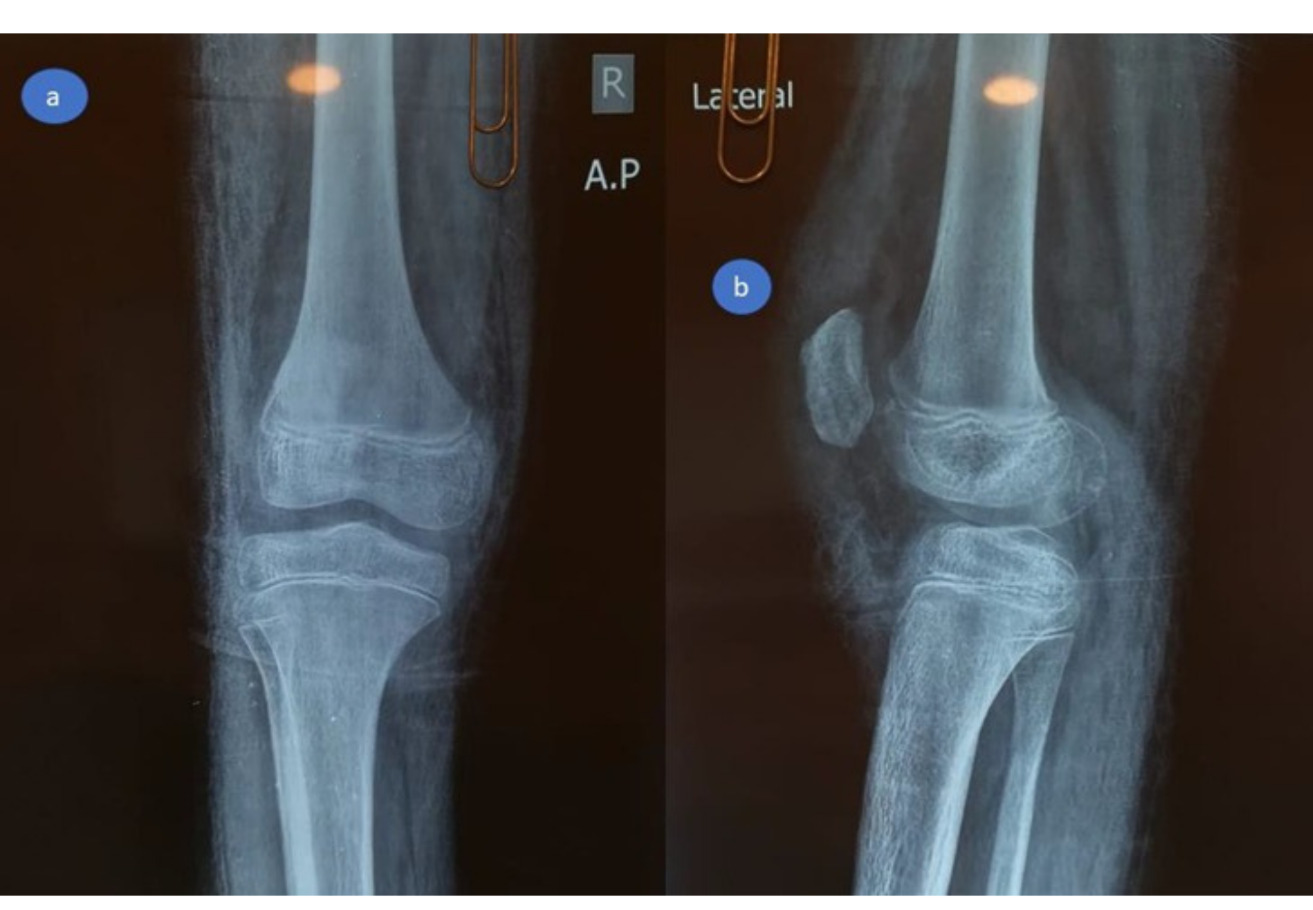

Young children are susceptible to a special kind of patellar fracture. These are called patellar sleeve fractures, and they affect the inferior pole of the patella. The patellar tendon, periosteum, and the distal articular cartilage will all avulse from the inferior surface of the patella, causing a disruption in the articular surface and the extensor mechanism (Papotto et al. 2024) (Figure 1A). Patellar sleeve fractures account for approximately 1% of all pediatric fractures and more frequently occur around 12 years of age (Ray and Hendrix 1992; Boushnak et al. 2020).Early detection and treatment of this condition are essential. Depending on the clinical and radiographic data, the diagnosis could initially be challenging and hard (Houghton and Ackroyd 1979; Grogan et al. 1990; Lin, Lin, and Wang 2011; Yeung and Ireland 2004).

These injuries commonly present with acute knee pain, limited range of motion, a joint effusion, and a palpable gap below the patella’s inferior pole. The diagnosis of patellar sleeve fractures is based in most cases on the presence of a high-riding patella, or patella alta, on the lateral plain radiograph. The Insall-Salvati ratio is used to calculate patellar height, with normal values ranging between 0.8 and 1.2. A ratio greater than 1.2 is indicative of patella alta, while a ratio below 0.8 suggests patella baja (Lin, Lin, and Wang 2011).

At the emergency room, radiographs were performed, which revealed a high-riding patella with a noticeable joint effusion as well as a small osteochondral fragment positioned distally to the patella. (Figure 2) As a result of the high-riding patella on the radiographs and the avulsion of the distal osteochondral side of the patella, a patellar sleeve fracture was detected. The surgery was scheduled for the next day.